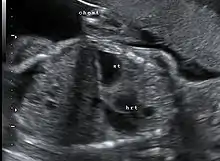

This condition can often be diagnosed before birth and fetal intervention can sometimes help, depending on the severity of the condition.[5] Infants born with diaphragmatic hernia experience respiratory failure due to both pulmonary hypertension and pulmonary hypoplasia. The first condition is a restriction of blood flow through the lungs thought to be caused by defects in the lung. Pulmonary hypoplasia or decreased lung volume is directly related to the abdominal organs presence in the chest cavity which causes the lungs to be severely undersized, especially on the side of the hernia.

Survival rates for infants with this condition vary, but have generally been increasing through advances in neonatal medicine. Work has been done to correlate survival rates to ultrasound measurements of the lung volume as compared to the baby's head circumference. This figure known as the lung to head ratio (LHR). Still, LHR remains an inconsistent measure of survival. Outcomes of CDH are largely dependent on the severity of the defect and the appropriate timing of treatment.